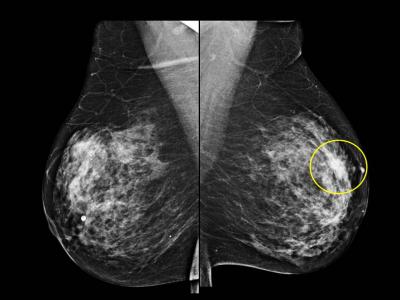

CHICAGO – In a study of screening mammography-detected breast cancers, patients who had more frequent screening mammography had a significantly lower rate of lymph node positivity—or cancer cells in the lymph nodes—as compared to women who went longer intervals between screening mammography exams. Results of the study were presented today at the annual meeting of the Radiological Society of North America (RSNA).

In its earliest stages, breast cancer is confined to the breast and can be treated by surgically removing the cancer cells. As the disease progresses, breast cancer cells may spread to the lymph nodes and then to other areas of the body.

"On its pathway to other places in the body, the first place breast cancer typically drains into before metastasizing is the lymph nodes," said Lilian Wang, M.D., assistant professor of radiology at Northwestern University/Feinberg School of Medicine in Chicago, Ill. "When breast cancer has spread into the lymph nodes, the patient is often treated both locally and systemically, with either hormone therapy, chemotherapy, trastuzumab or some combination of these therapies."

The retrospective study, conducted at Northwestern Memorial Hospital, included 332 women with breast cancer identified by screening mammography between 2007 and 2010. The women were divided into one of three groups, based on the length of time between their screening mammography exams: less than 1.5 years, 1.5 to three years and more than three years. There were 207, 73 and 52 patients in each category, respectively.

Controlling for age, breast density, high-risk status and a family history of breast cancer, the researchers determined that women in the less than 1.5-year interval group had the lowest lymph node positivity rate at 8.7 percent. The rate of lymph node involvement was significantly higher in the 1.5- to three-year and over three-year interval groups at 20.5 percent and 15.4 percent, respectively.

"Our study shows that screening mammography performed at an interval of less than 1.5 years reduces the rate of lymph node positivity, thereby improving patient prognosis," Dr. Wang said. "We should be following the guidelines of the American Cancer Society and other organizations, recommending that women undergo annual screening mammography beginning at age 40."